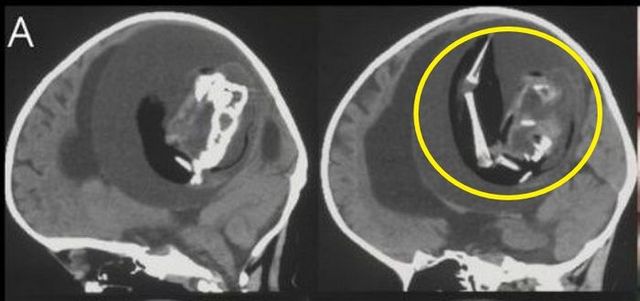

두개골에서 발견된 기생 태아ⓒ트위터 갈무리 두개골에서 발견된 기생 태아ⓒ트위터 갈무리

중국에서 태어난 1세 아이의 두개골에서 '일란성 쌍둥이 태아'가 발견됐다.

9일(현지시간) 영국 데일리스타에 따르면 중국 푸단대학 병원 의사들은 1세 아이의 두개골 안에서 일란성 쌍둥이의 태아를 제거했다.

이 아이는 대두증과 운동 능력 상실 등이 의심돼 부모와 함께 병원을 찾은 것으로 전해졌다. 의료진은 아이의 머리에 종양이 있을 것으로 생각했고, 즉시 CT 촬영을 실시했다.

검사 결과는 충격적이었다. 아이의 두개골 안에 종양이 아닌 '태아'가 웅크리고 있었기 때문이다. 태아는 두개골 안에서 혈관을 공유하며 뇌를 짓누르고 있었다.

태아는 아이가 산모의 자궁에 있었을 당시에도 존재했으며, 연결된 혈관으로부터 뼈와 팔, 손까지 발달한 상태였던 것으로 전해졌다.

아이는 두개골 안에서 자리를 차지하고 있는 태아 때문에 뇌 일부분에 척수액이 고이는 증상인 수두증(물뇌증)을 앓고 있었다.

DNA 분석 결과 태아는 아이의 쌍둥이였던 것으로 조사됐다. 도태돼야 하는 분리된 수정란이 전뇌로 발달하면서 이 같은 현상이 발생한 것이다.

전문의는 이번 사례가 '쌍생아 소실'(Vanishing twin)의 희귀 사례로, 전 세계에서 약 200번밖에 기록되지 않은 극히 드문 경우라고 밝혔다.